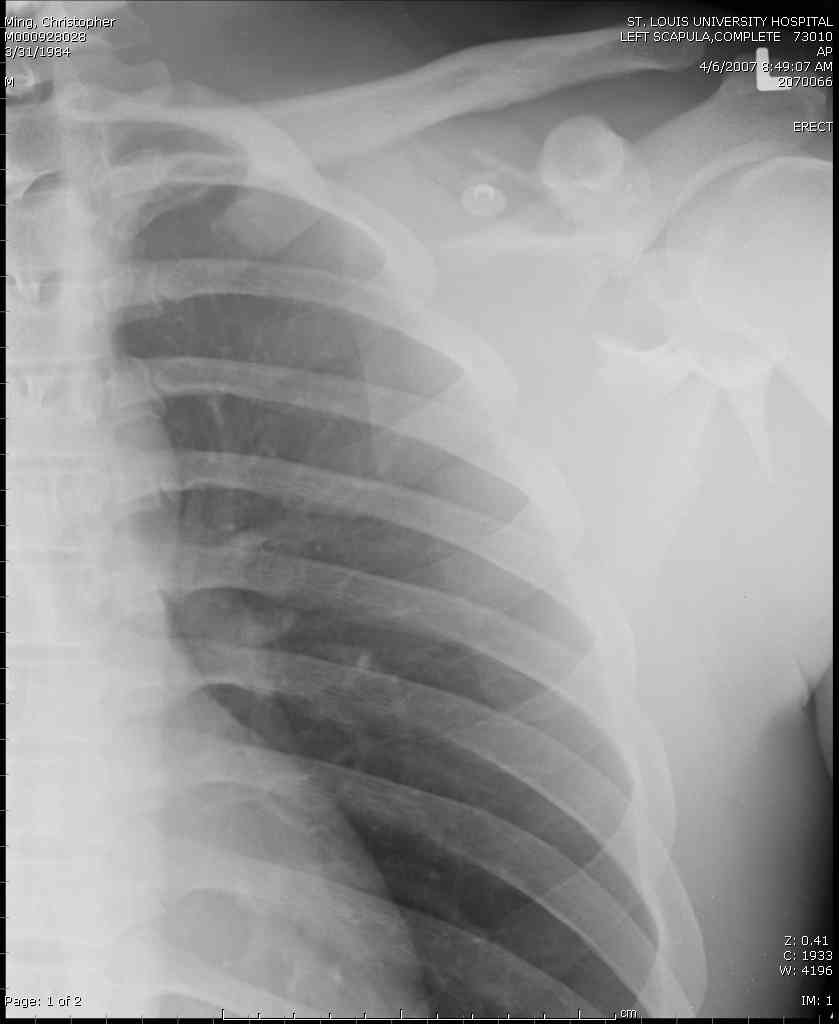

дравствуйте, коллеги. Мужчина 24 лет. Сегодня был прооперирован по Сушко-Илизарову (давно порывался, наконец-то руки дошли :)) На снимке перелом угла лопатки. Довольно крупный размер осколка. Следует ли оперировать такой перелом?Если есть резон оперативного лечения, то каким образом? (рекон. пластина, закрыто пришпилить спицами, винтами). ЭОПа в наличии нет. В области лопатки массивный отек мягких тканей. С уважением, Заднепровский Никита Николаевич

А где там сломанный угол лопатки? Стрелочкой покажите pls?

Для решения насчет оперативного вмещательства на лопатке сперва надо определиться с обьязательными ренгенологическими исследованиями, не менее трех стандартных проекций: прямая, аксиллярная и в позиции виде “Y”.

Прямую снимают под углом в 35 градусов от центра и вид “Y” в 90 градусов к нему. Несмотря на неудобства, больному необходимо сделать

аксиллярный снимок.

К-томографические и Трехмерные(3D)снимки крайне важны для определения внутрисуставных переломов и классификации.

Посмотрел пациента под рентгеноскопом, определяется изолированный перелом верхнего медиального угла лопатки. Вопрос об операции отпал. Больной машет крылом как пропеллером, пришлось ограничить активность дисциплинирующей "косынкой" ... :))) Отек мягких тканей в области